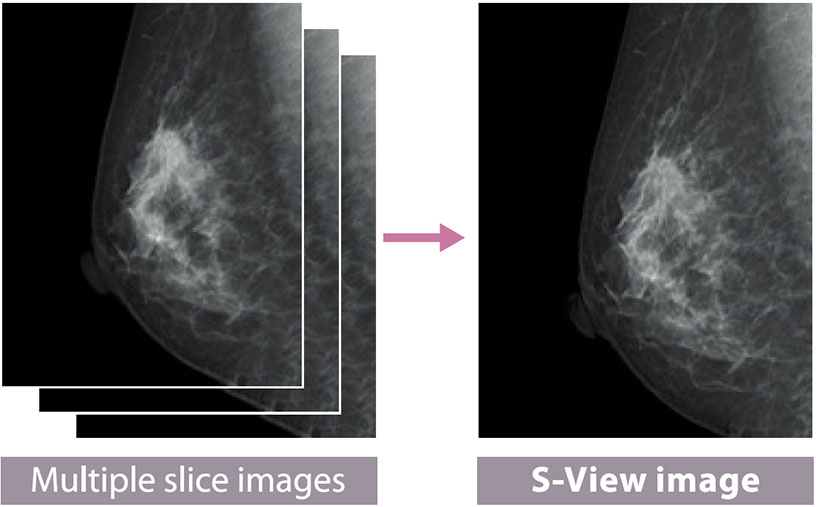

S-View(synthesized 2D image)function is available

Tomosynthesis by AMULET Innovality automatically produces not only tomograms obtained at 1 mm intervals but also a two- dimensional S-View image combining multiple slice images.

With the S-View image showing the overall view added to tomograms offering the views in detail, comprehensive image reading is possible.